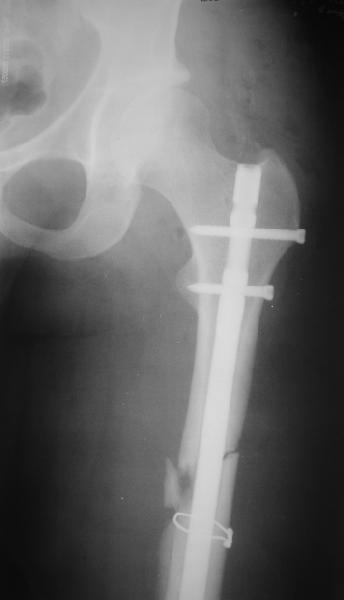

Пациент попал под наше наблюдение через 3 недели после первого остеосинтеза (фото 1). Учитывая, нестабильность остеосинтеза, выстоящий стержень закрыто перештифтовали (фото 2), через 3 месяца динамизация. К 5 месяцам имели укорочение 2 см, при том, что динамический винт стал статическим. От дальнейшей динамизации отказались, учитывая наличие контакта между фрагментами и возможность прогрессирования укорочения. К 1,5 года сращение не достигнуто (фото 3). Удалили гвоздь, выполнили дистракционный остеосинтез с целью стимуляции остеогенеза и компенсации укорочения (фото 4), потом закрыто перештифтовали после рассверливания (фото 5). На сегодняшний день, через 4 месяца после последней операции (фото 6) признаков регенерата нет, длина восстановлена, ходит без дополнительной опоры.

Возможные варианты: 1)подождать - однако регенерата не заметно 2)Снова потерять длину (динамизация, компрессирющий остеосинтез на этом гвозде, после перепроведения проксимальных винтов и копрессирующей заглушки, восстановление длины после сращения) 3)Костная пластика